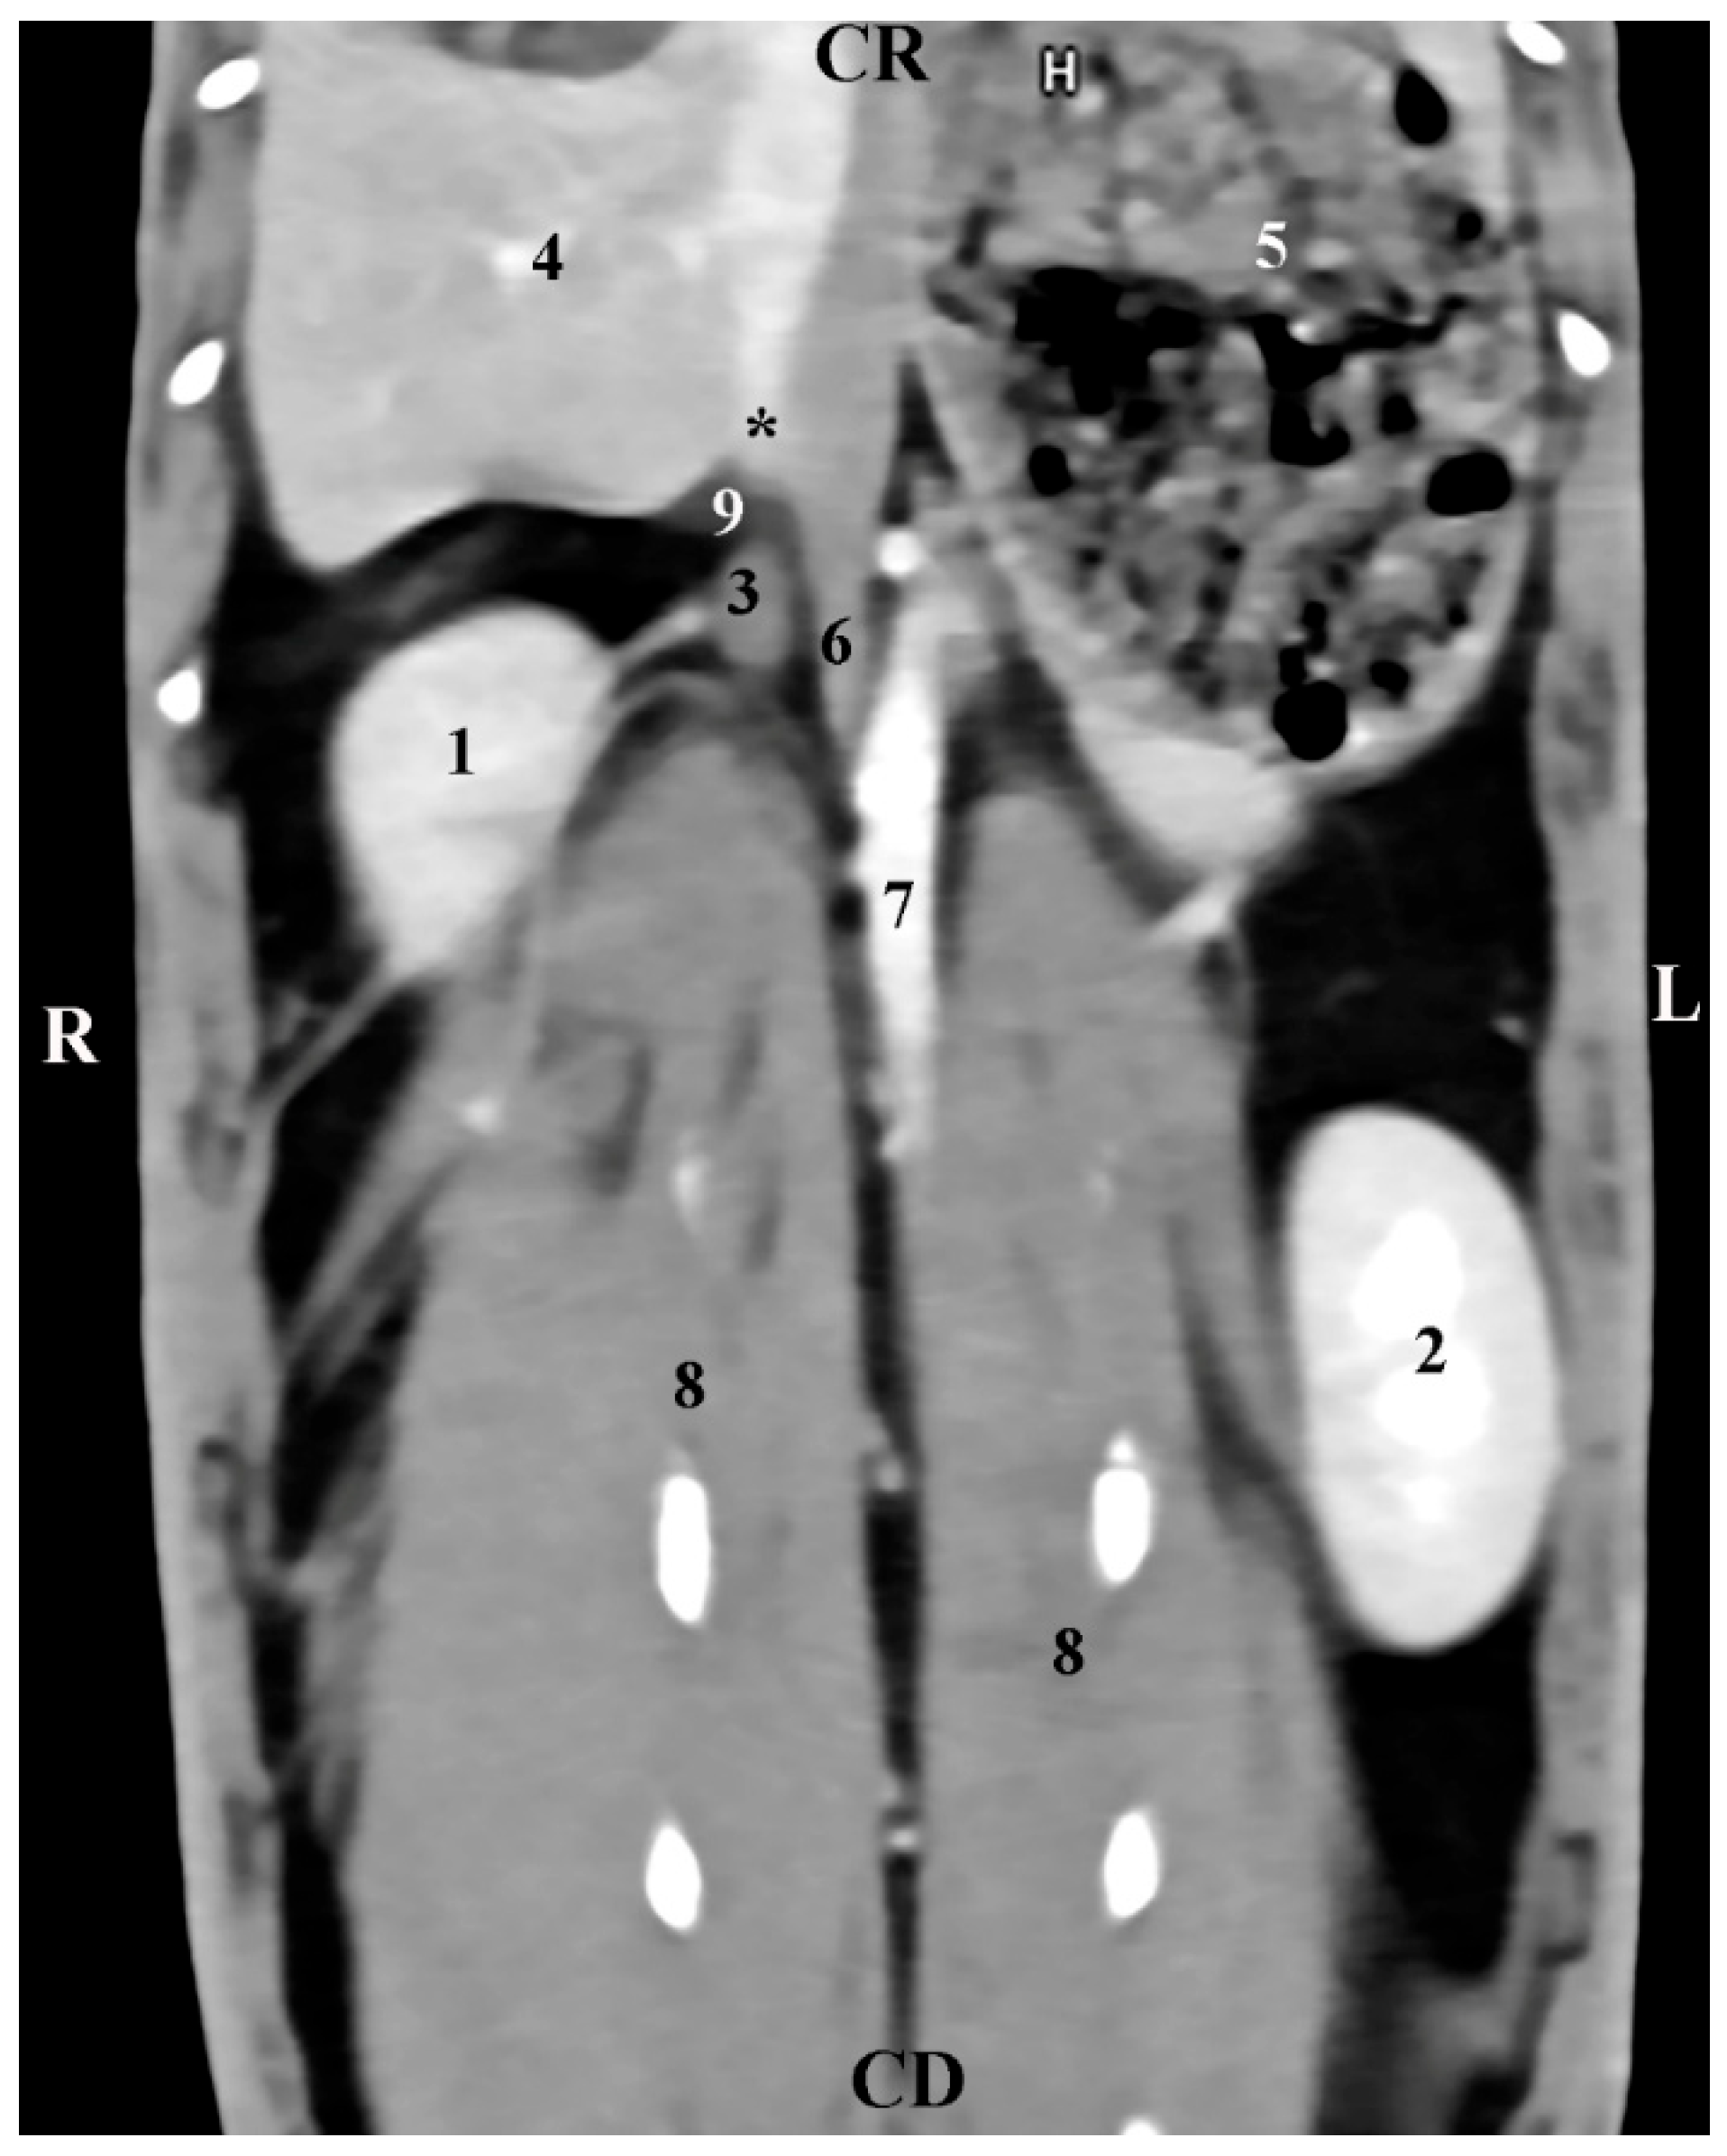

The left adrenal gland was visualized at the level of the 1st lumbar vertebra (L1). It was left to the median plane and in the dorsal abdominal cavity quarter. The gland was visible at a more caudal level of scanning compared to the right adrenal. gl. adrenalis sinistra had oval contours and was observed ventrally to the contrast-enhancing abdominal aorta and distant and craniomedially to the left kidney. The left adrenal density was similar to that of the ventrally located mesentery (Figure 2).

Figure 2. Transverse CT post-contrast anatomical study of the rabbit abdomen at the level of L1. L—left; R—right. (1) aorta abdominalis; (2) v. cava caudalis; (3) left adrenal gland; (4) right kidney; (5) small intestine; (6) mesenterium; (7) colon descendens; (8) colon ascendens; (9) caecum; (10) lien.